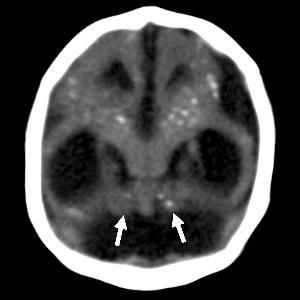

Intracranial calcifications were present in almost all of the neonates, most commonly found at the gray-white junction of the brain. All of the babies exhibited reduced tissue volume in their brains. All patients showed varying abnormalities in cortical development.

"The severity of the cortical malformation and associated tissue changes, and the localization of the calcifications at the grey-white matter junction were the most surprising findings in our research," Dr. Tovar-Moll said.

Figure 4. Images obtained in the case of an 18-year-old woman, first seen for rash at 10 weeks of pregnancy, with confirmed Zika virus infection. US findings obtained at 20 weeks of gestational age were reportedly normal, with normal head circumference of 17.5 cm. At 37 weeks of gestational age, (a) sagittal transvaginal and (b) coronal transabdominal US images obtained with the head upside down show a small head circumference (26.4 cm, corresponding to 28 weeks 5 days, below the 3rd percentile), moderate ventriculomegaly with dense intracranial calcifications (arrowheads on a), and abnormal head shape with flattened appearance and thickened skin (arrow on a). On the sonogram, it is difficult to precisely localize the calcifications, given the thin parenchyma. (c, d) Axial bone window CT images, (e) sagittal localizer CT image, and (f–h) axial CT images show microcephaly with cerebral atrophy, and, despite ventriculomegaly, the extra-axial cerebrospinal fluid spaces are still prominent. The hypoattenuating calcifications are predominantly located in the subcortical white matter at the gray matter–white matter interface. There is markedly abnormal skull shape with some eversion of the bones at the suture sites (particularly frontoparietal sites), with redundant skin folds (particularly in the parieto-occipital region). (i) Sagittal T1-weighted, (j, k) coronal T2-weighted, and (l) axial susceptibility-weighted MR images obtained at 1 month of age show an undersegmented midbrain, severe microcephaly, open sylvian fissures, and polymicrogyria. The dense calcifications are evident on the susceptibility-weighted image. On the sagittal images (a, e, i), note the small supratentorial compartment and associated skull deformity.